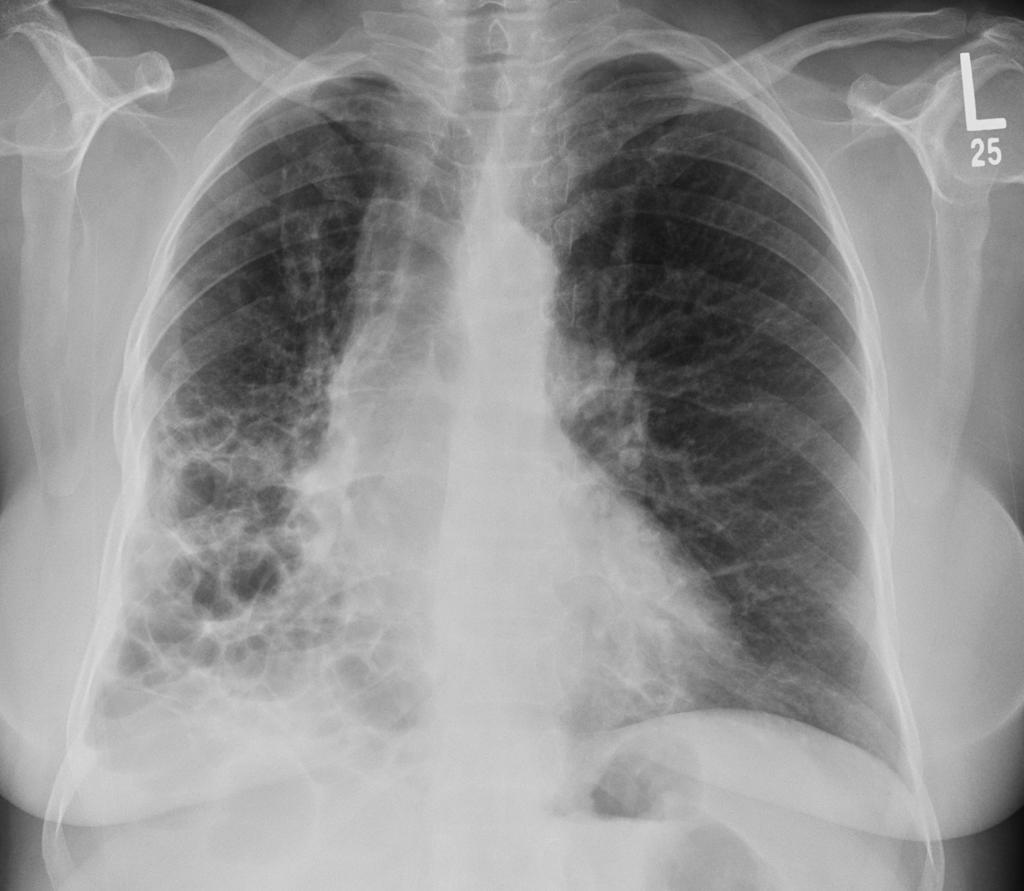

间质性肺疾病的病理生理机制

间质性肺疾病的病理机制虽然复杂,但通过深入了解这些机制,我们就能更好地利用营养干预来对抗疾病。 营养不是万能的,但在疾病的防治中确实发挥着不可替代的作用。 ...

间质性肺疾病的疾病概述与定义

提到肺病,大多数人想到的可能是肺炎、肺癌这些"知名度"比较高的疾病,但有一类肺病却像个"隐形杀手",悄悄地损害着我们的肺部,它就是间质性肺疾病,简称ILD。 ...